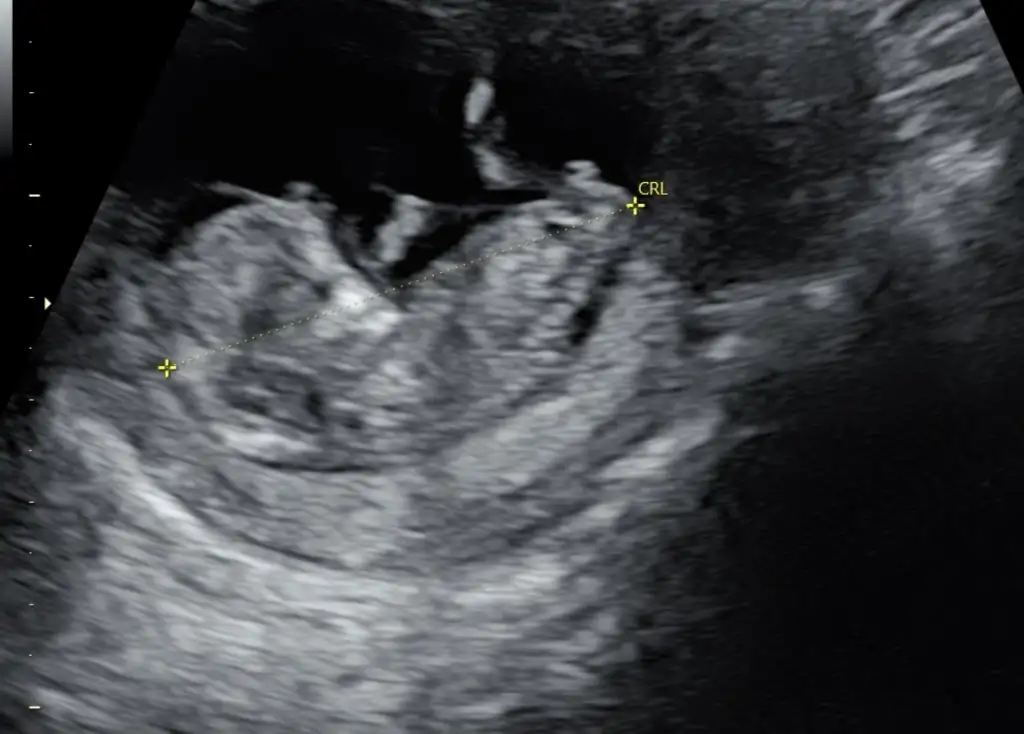

IMG_4362.webp

Bizim için cinsiyet tahmini yapabilecek var mı 🥰